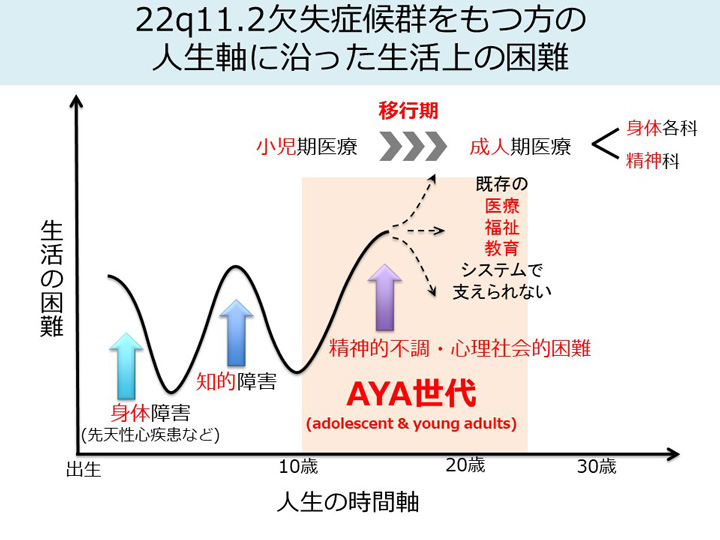

Z/X -Zillions of enemy X- NC DramaCD ① 「超鋼神器。22q11.2欠失症候群とは | 22q-pedia。107I76 | 心室頻拍 国試 | テコプラ。「異常心理学」村瀬 孝雄 / G.C.デビソン / ジョン・M・ニール定価: ¥ 15000#村瀬孝雄 #村瀬_孝雄 #GCデビソン #G_C_デビソン #ジョン・M・ニール #本 #心理学/心理学蔵書印あり。Z/X -Zillions of enemy X- NF DramaCD ⑨ 「13姉妹 雪月花。カバー背表紙にシール剥がし痕あり。歴史を偽造する韓国 : 韓国併合と搾取された日本。ご理解いただける方に。消防官、本セット。